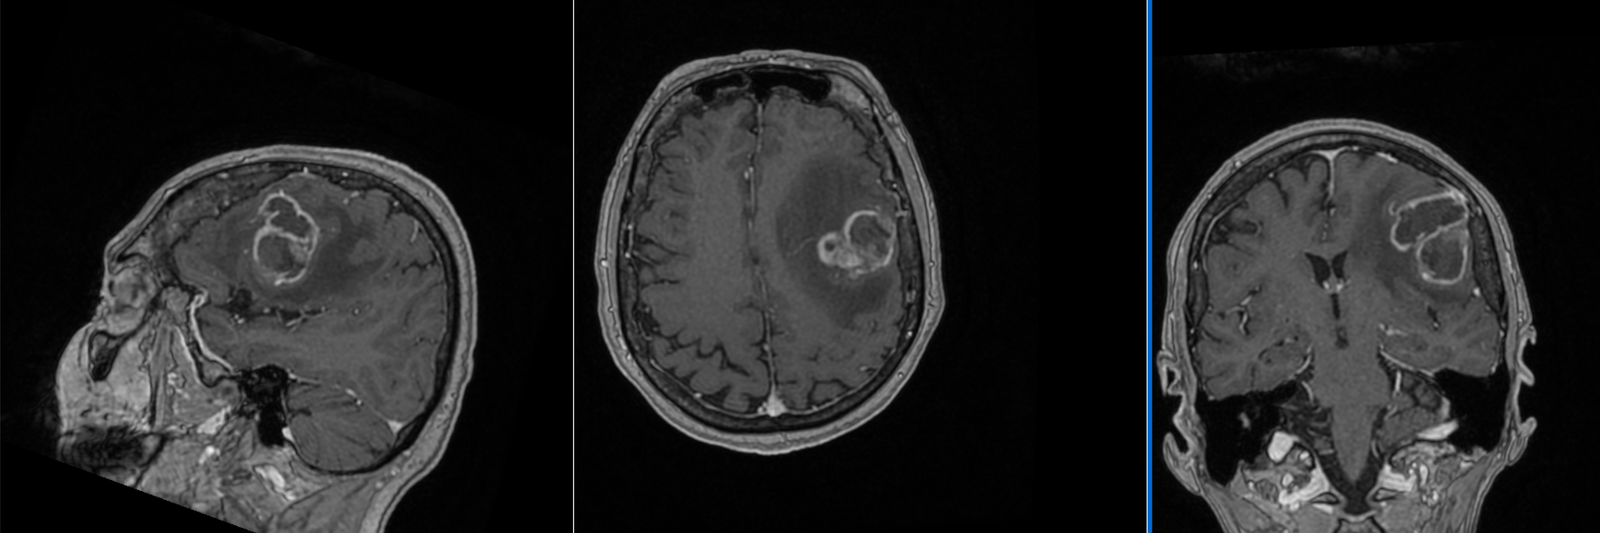

La nivel imagistic, glioblastomul apare adesea ca o leziune relativ bine delimitată, cu captare inelară de contrast și necroză centrală. Pentru ochiul neavizat, aceasta poate sugera o tumoră care ar putea fi „scoasă complet”. În realitate, ceea ce vedem pe RMN reprezintă doar componenta cea mai densă tumoral.

Imagistica – instrument esențial, dar imperfect

RMN-ul cerebral este standardul diagnostic, dar trebuie interpretat în context.

Pe lângă secvențele convenționale, tehnicile avansate aduc informații suplimentare:

- perfuzia evidențiază angiogeneza tumorală

- spectroscopia reflectă metabolismul celular

- DTI (tractografia) arată relația cu tracturile din substanța albă

Cu toate acestea, niciuna dintre aceste metode nu poate delimita complet infiltrarea microscopică. De aceea, planificarea chirurgicală și terapeutică trebuie să țină cont de această limitare.